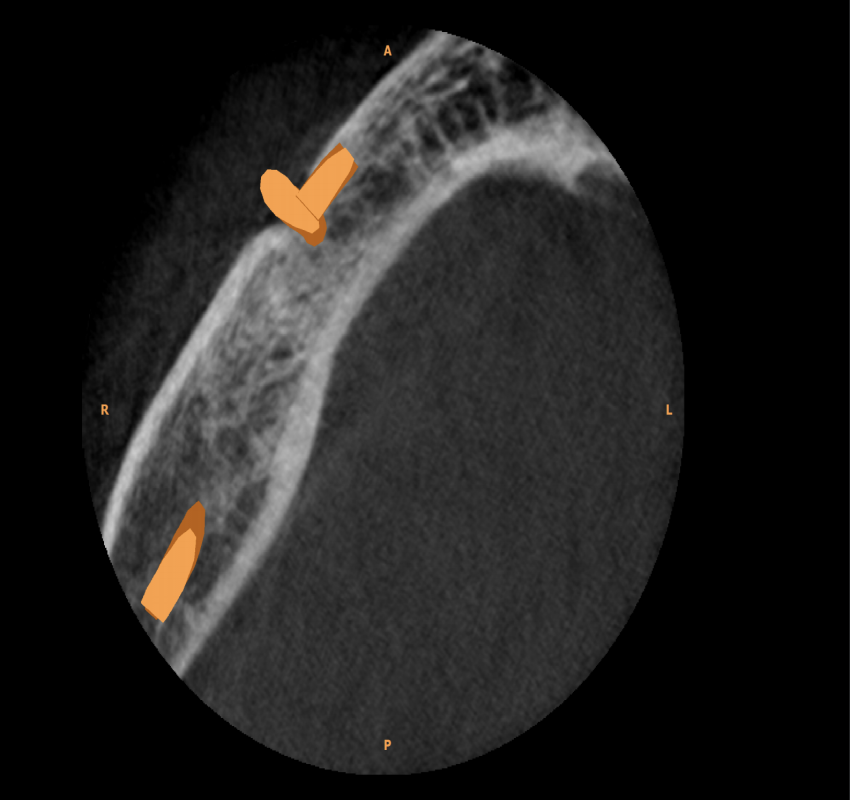

Dentistry has witnessed tremendous advances in all its branches over the past three decades. With these advances, the need for more precise diagnostic tools specially imaging methods has become mandatory. From the simple intraoral periapical x-rays, advanced imaging techniques like computed tomography, cone beam computed tomography, magnetic resonance imaging and ultrasound have also found their place in modern dentistry.

Changes from analouge to digital radiography has not only made the process simpler and faster but also made image storage and manipulation and retrieval easier. The 3- D imaging has made the complex craniofacial structures more accessible for examination.